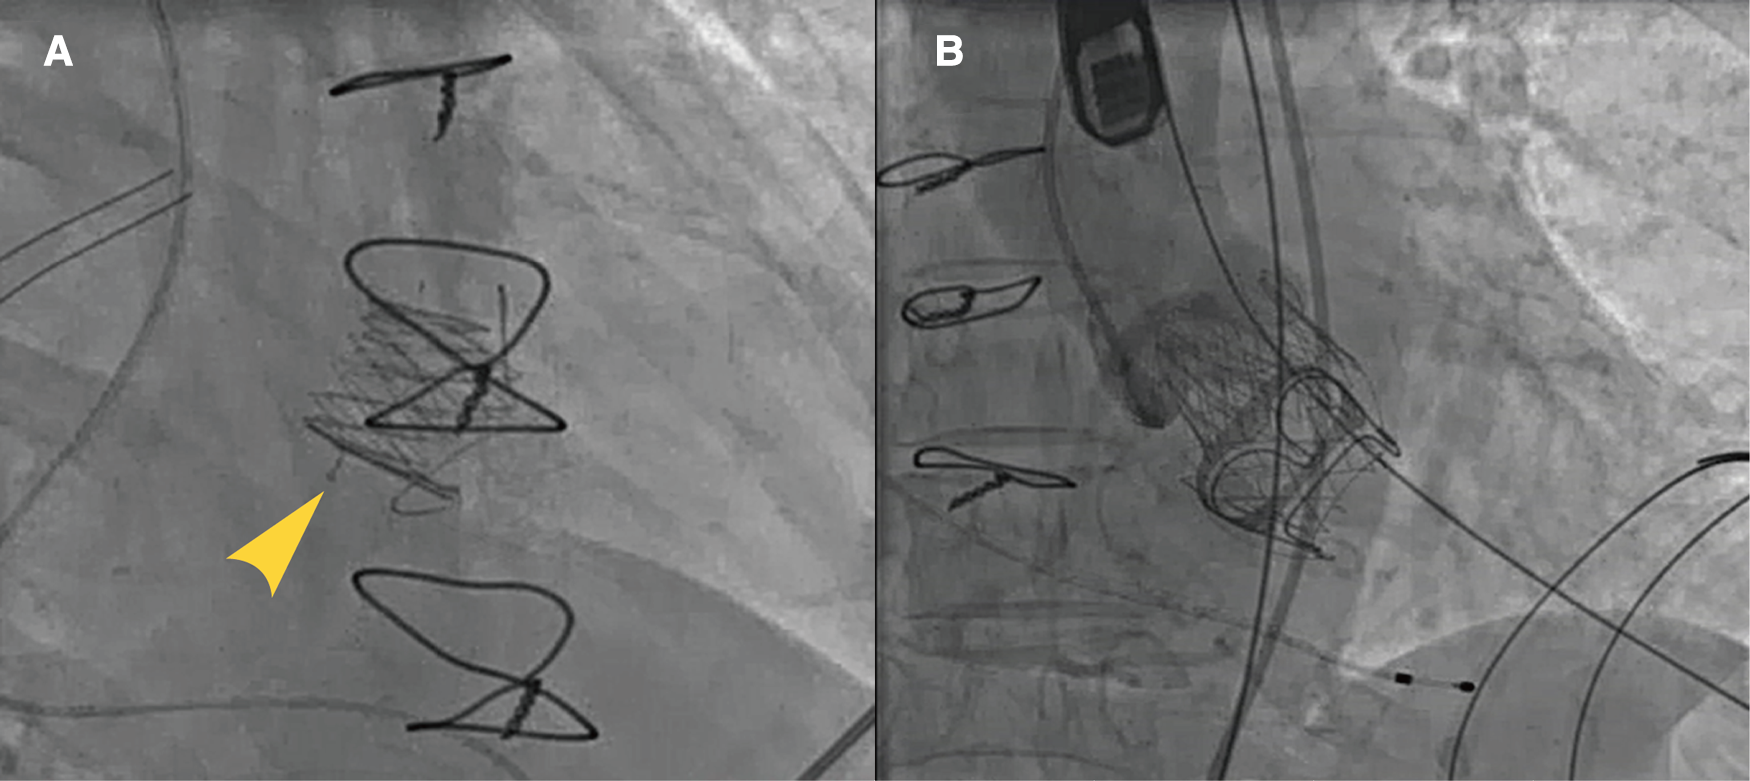

Figure 3

Typical cases of utilization of J-Valve. J-Valve applied to a strut-radiolucent epic valve (St Jude Medical) for ViVTMVR (A). Combined aortic valve disease with concomitant TAVR and ViV-TMVR procedures (B).

The step-by-step procedure is shown in Figure 2 and Supplementary Video S1. After apical puncture, the failing bioprosthetic mitral valve can usually be crossed easily using J-tip guidewires. A transesophageal echocardiography was used to further confirm the guide wire into the left atrium. The wire was subsequently exchanged for an extra-stiff guide wire with curved tip. Conveyor curvature could be adjusted as needed to provide optimal coaxiality. After entering the left ventricle along the extra-stiff guidewire (Figure 2A), the conveyor first released three U-shaped grippers and subsequently staggered them between three struts of the bioprosthetic valve (Figure 2B). To improve the success and accuracy of this step, a preoperative computed tomography assessment was performed to calculate the C-arm angle at which the tips of the three struts are located at the same level. This is particularly important for the epic valve (St Jude Medical, Inc, St Paul, MN, USA) because its struts are radiolucent (Figure 3A). The valve was slowly released under rapid ventricular pacing (Figure 2C). Subsequently, the conveyor anchor device was controlled to de-load the valve (Figure 2D), the conveyer was withdrawn, and the guidewire retained (Figure 2E). Mitral flow velocity and paravalvular leak were explored using transesophageal echocardiography. Detection of mitral flow velocity and paravalvular leak using transesophageal echocardiography were utilized to determine whether to perform balloon valvuloplasty. The ideal implantation depth was considered to be 80% of the THV stent frame in the left ventricle and 20% in the left atrium (Figure 2F). Coincident native aortic valve disease or prosthetic bioprosthetic valve failure can also be managed concurrently (Figure 3B).

Our center was the first to successfully complete ViV-TMVR using a reverse-loaded J-Valve in January 2019. ViV-TMVR was accomplished in an innovative way by changing the loading direction and release sequence without changing the structure of the J-Valve and conveyors. J-Valve has several advantages when applied to ViV-TMVR. First, its three grippers make leaflet-to-leaflet and commissure-to-commissure positioning simple, without the need to consider commissural misalignment (Figure 1B). The problem of misalignment due to ViV-TMVR has until now been largely ignored in clinical research. Correct orientation is mandatory for surgical bioprosthetic valve replacement (28), which means that commissural posts should not face the LVOT. The risk of LVOT obstruction may be increased if the THV commissure posts point toward the LVOT. There is however no way of preventing misalignment for balloon-expandable THV. Second, J-Valve also has U-shaped notches (Figure 1B) instead of a complete cylindrical metal stent, which minimizes the risk of LVOT obstruction and has particular advantages in patients with small left ventricular volumes (29), meaning that an evaluation of the neo-LVOT is not required (30). Third, because of the fixation of the grippers, the risk of the potentially fatal distant THV migration to the left atrial side (7–10) was reduced. Fourth, J-Valve can be used for both ViV-TAVR and ViV-TMVR, and even for tricuspid bioprosthetic valve failure, which allows valve-in-valve transcatheter tricuspid replacement (ViV-TTVR) using a right atrial approach. Fifth, the self-expanding THV can continuously apply a radial support force on the failed bioprosthetic valve's stents, so that the failed leaflets remain strongly anchored at the frame.